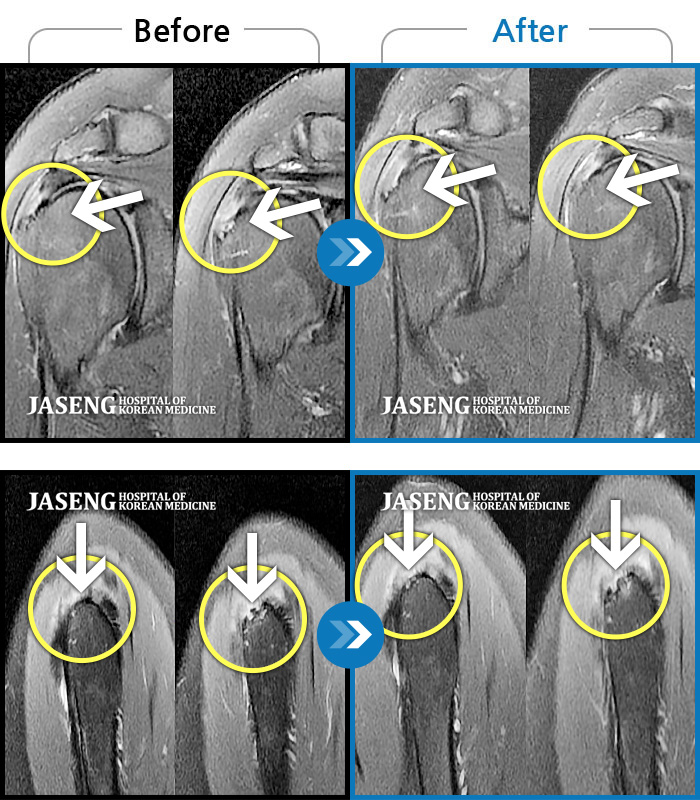

관절질환

도움받은 사례

대전 · 김창연

넘어질때 손을 짚으면서 우측 어깨에 심한 충격이 오고 이후로 심한 어깨 통증으로 일상생활이 힘든 상태로 내원하였습니다.

촬영시기

2022.02.04 ~ 2022.05.06

2022.05.13

조회수 331